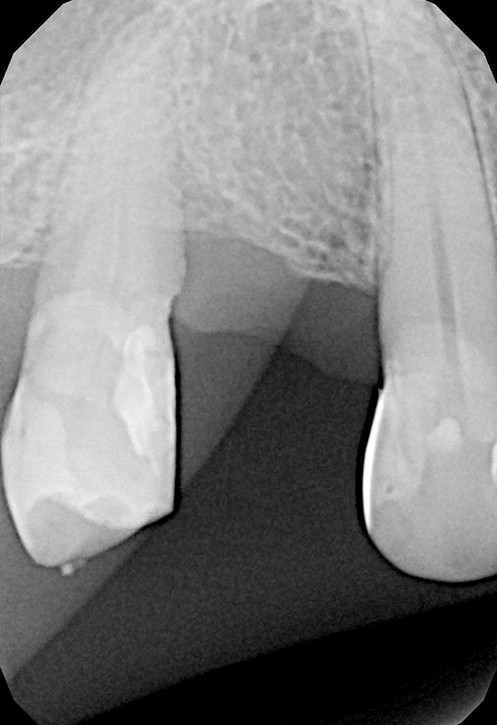

Konieczność powtórnego leczenia endodontycznego może zaistnieć w sytuacji, gdy kanały zęba nie zostały wypełnione do ich anatomicznego wierzchołka lub w trakcie leczenia doszło do złamania i pozostawienia ułamanego narzędzia w świetle kanału korzeniowego. O konieczności powtórnego leczenia endodontycznego może również zadecydować zmiana zapalna przy wierzchołku korzenia, która jest widoczna jedynie na obrazie kontrolnego zdjęcia rtg.

Prawidłowo wyleczony endodontycznie ząb z powodzeniem może służyć przez wiele lat życia pacjenta. Poprawa jego funkcji możliwa jest dzięki skutecznej odbudowie protetycznej, poprzez wzmocnienie go wkładami koronowo-korzeniowymi z włókna szklanego i wykonanie korony protetycznej.

By uniknąć niedokładności leczenia, oprócz sumiennego wykonania procedur należy diagnostycznie kontrolować każdy etap leczniczy przy użyciu rtg. Szansą dla niedokładnie wypełnionego kanałowo zęba jest jego powtórne leczenie endodontyczne, zwane REENDO.